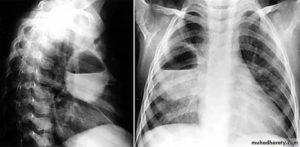

Начальную стадию абсцесса очень легко выявить с помощью рентгеновского снимка.

Выполнив рентгеновский снимок в различных проекциях, выявить на нём наличие абсцесса легких можно по присутствию таких факторов:

- выделение признаков, характерных для наличия круглой тени;

- присутствуют нечёткие границы (может свидетельствовать о том, что заболевание сопровождается воспалительным процессом);

- интенсивность средней степени;

- выделяется однородность содержимого (указывает на наличие гнойника);

- рядом с пораженной стороной наблюдается увеличение размеров лимфатических узлов в корне;

- имеется полость распада, которая размещена в средней области просветления;

- утолщенные стенки, при этом внутри они не являются равномерными;

- повышенный или пониженный уровень жидкости во внутренней зоне кольца.

Рентгенограмма абсцесса лёгкого на различных стадиях развития болезни может показать абсолютно разные картины.

На ранних стадиях развития болезни на снимке присутствуют следующие проявления:

- Во время первичных стадий абсцесса пораженная зона небольшая, от 1 до 4 см.

- Вокруг кольцевидной тени размещены очаги воспаления перифокального типа.

- Происходит деформирование легочного рисунка.

- Присутствует тенденция к возрастанию уровня жидкости.

По истечении некоторого времени внутренняя часть стенки кольцевидной тени подвергается уплотнению, и в результате этого исчезают её шероховатости.

На ранних стадиях снимок рентгена не дает четкой картины заболевания и может выглядеть, как очаговая пневмония, например.

Характерной особенностью снимка грудной клетки на этой стадии является наличие затемненности с неровными контурами в легочной области.